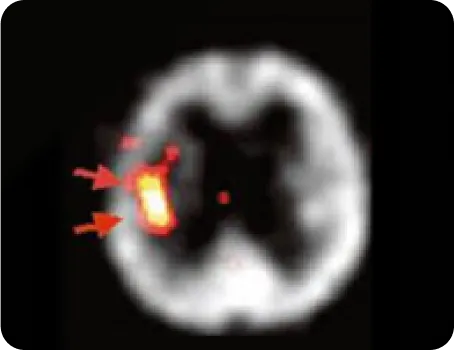

반음영 부위를 아시나요?

반음영 부위(Penumbra)란 뇌경색이 발생하여 혈류공급이 감소되었지만 완전히 죽지는 않은 조직을 말합니다.

이미 죽은 조직(Dead Tissue)의 붓기가 빠지면서 반음영 부위가 회복될 수 있는 6개월의 기간 동안 얼마나 뇌혈류를 개선시키고 뇌에 자극을 주느냐에 따라 평생을 따라다닐 후유증을 최소화할 수 있습니다.